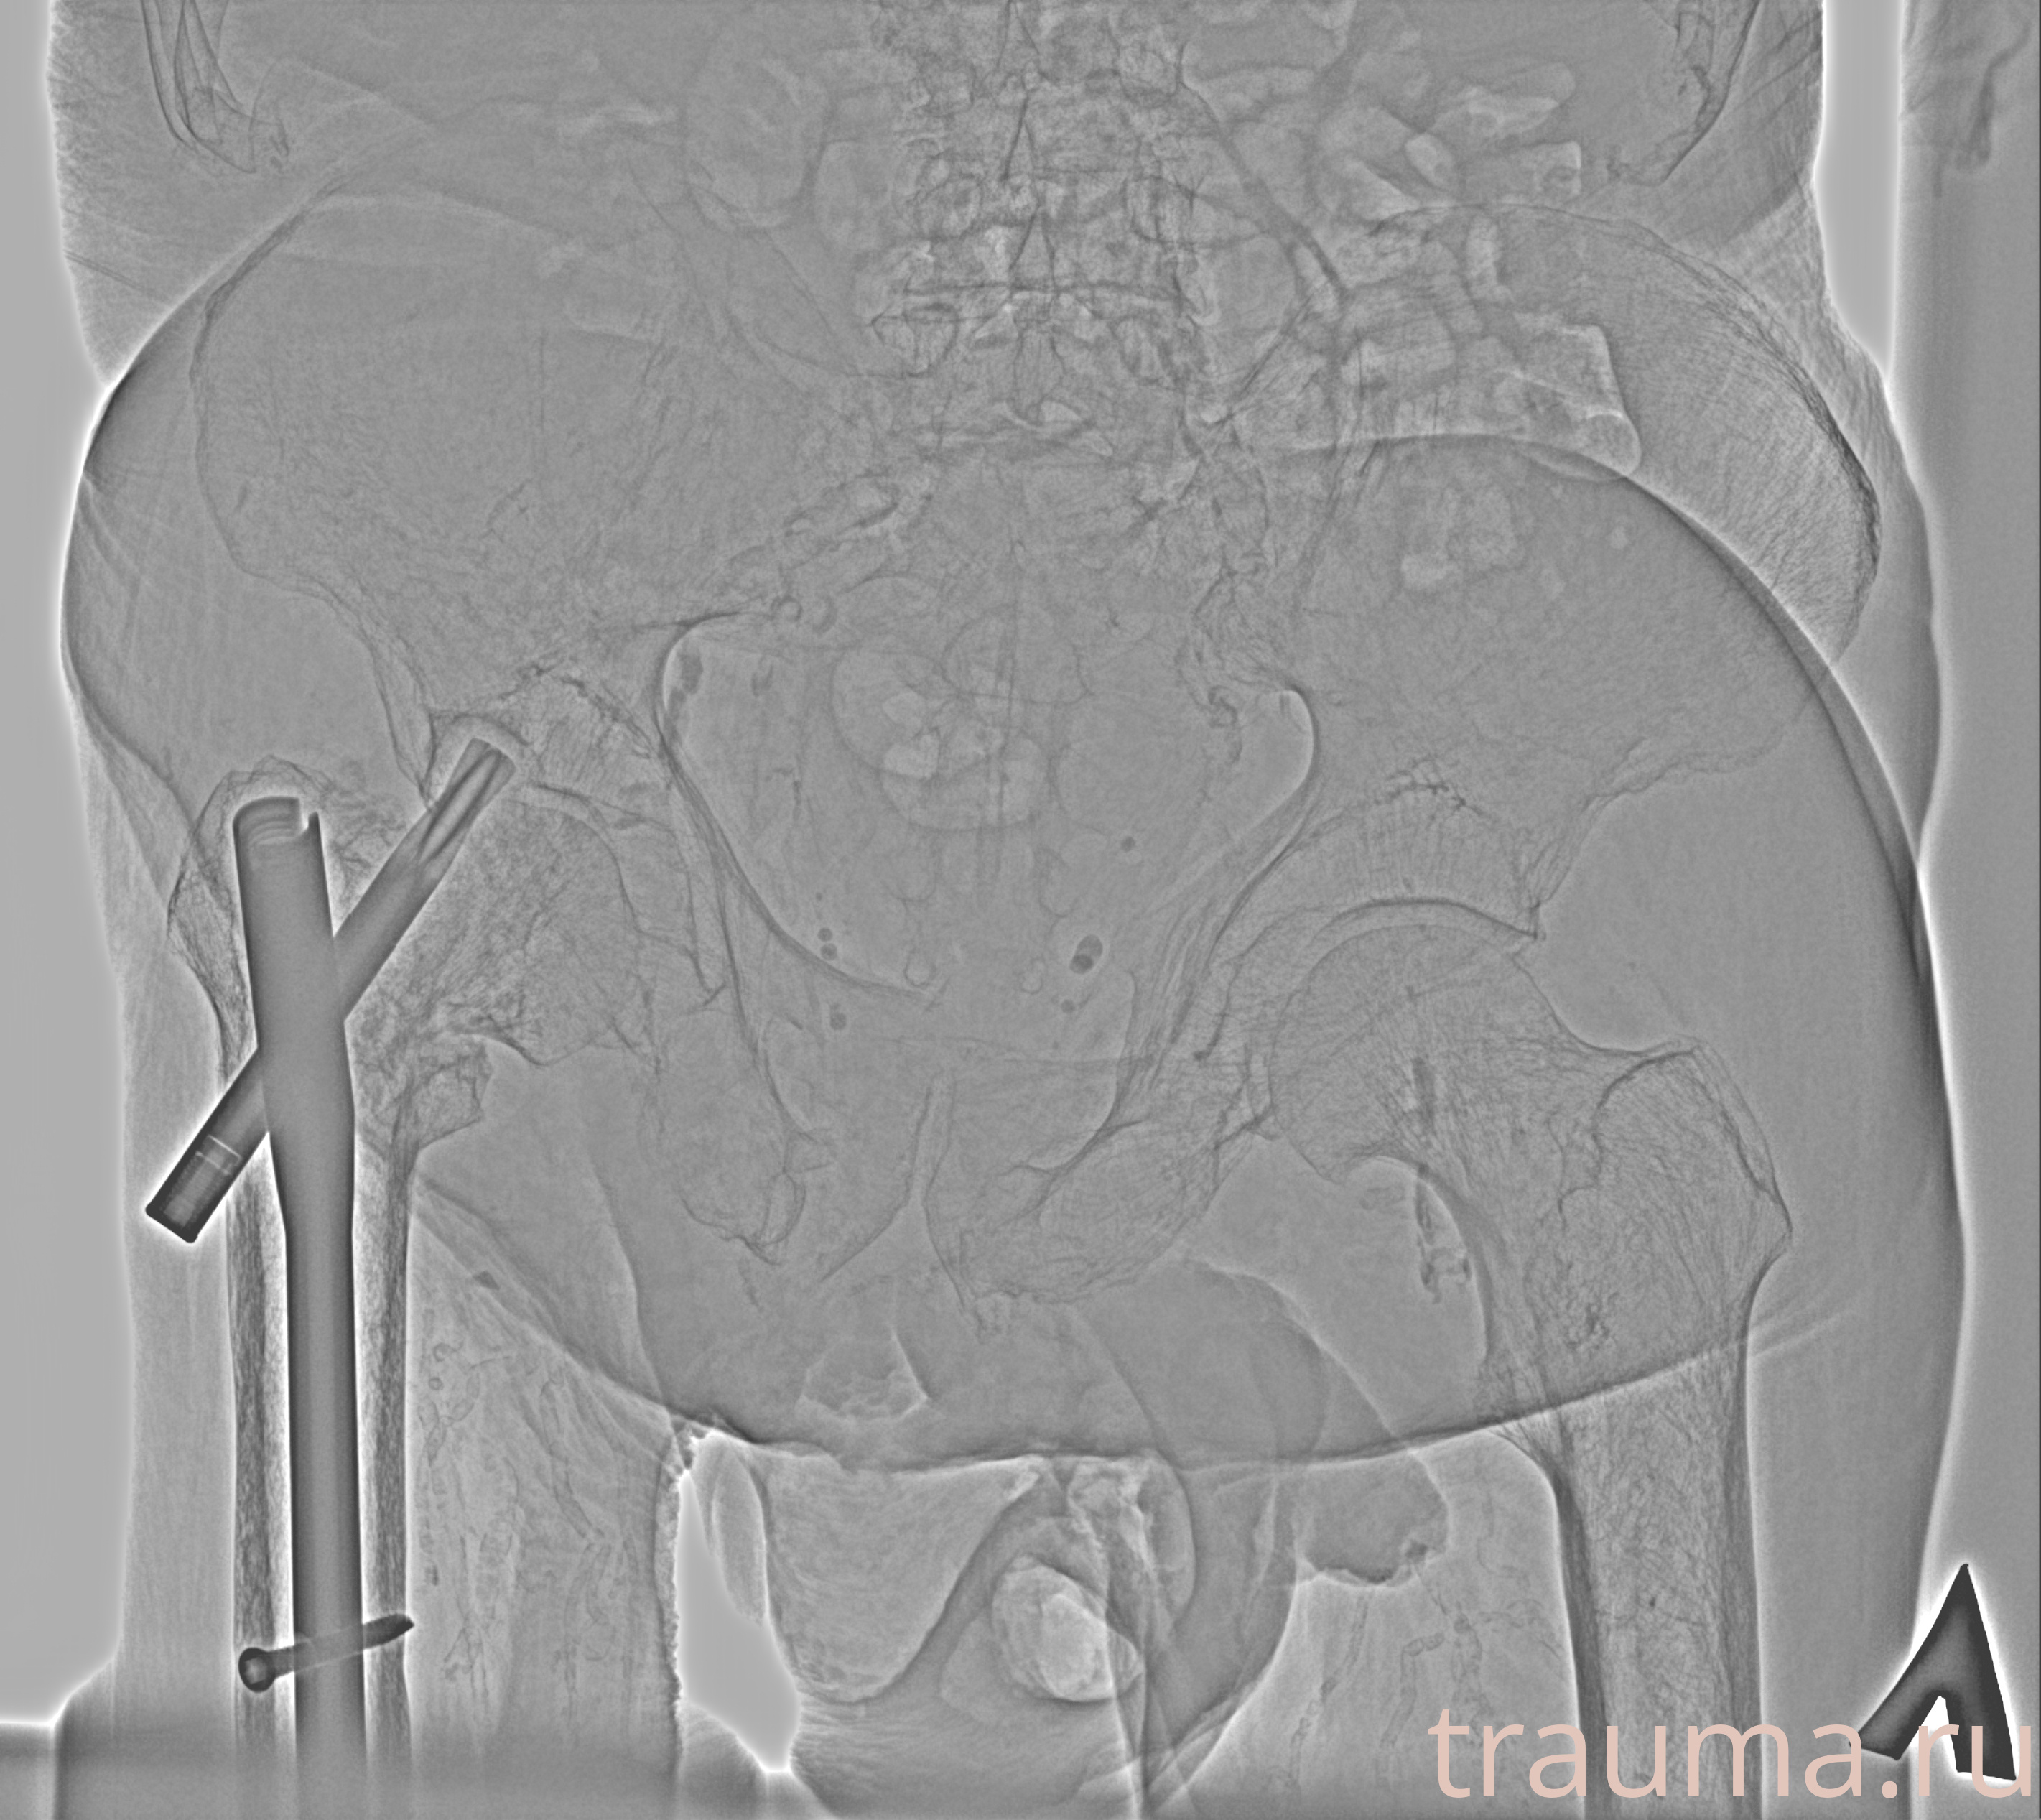

Рентген на дому: по вашему адресу приезжает врач-рентгенолог, травматолог-ортопед с мобильным рентгеновским аппаратом, проводит диагностику травмы или заболевания, делает необходимые рентгенограммы, дает рекомендации по дальнейшему лечению. Получить качественные снимки в домашних условиях возможно благодаря уникальной методике, разработанной МосРентген Центром для института  Склифосовского